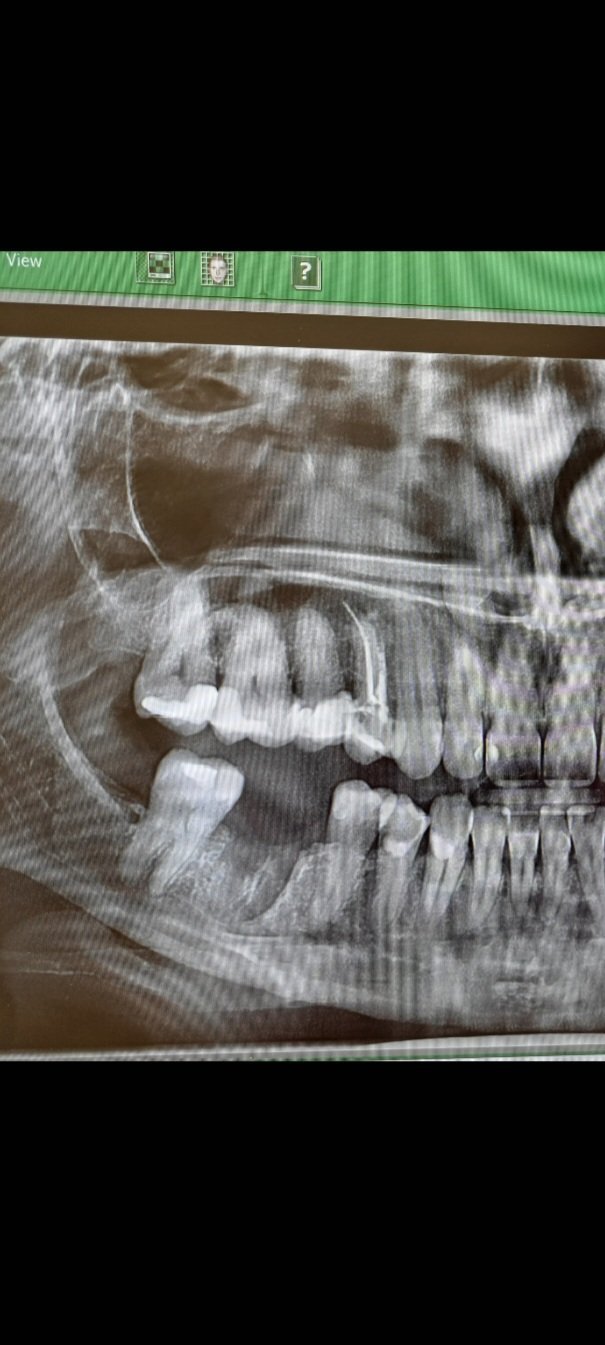

Кое е по-добро - импланти или мостове?

Имплантите и мостовете имат своите предимства и недостатъци. Имплантите често се рекламират, но не винаги са успешни в дългосрочен план. Те изискват определени условия на организма, които могат да увеличат шансовете за успешно интегриране в костта. Освен това поставянето на имплант може да бъде по-скъпо и не гарантира по-голям процент на успеваемост. Мостовете, от друга страна, могат да бъдат поставени по-бързо и по-евтино, но изискват изпиляване на съседните зъби. Всеки случай трябва да бъде оценен индивидуално от имплантолог, който може да предложи най-подходящото решение за конкретния случай.